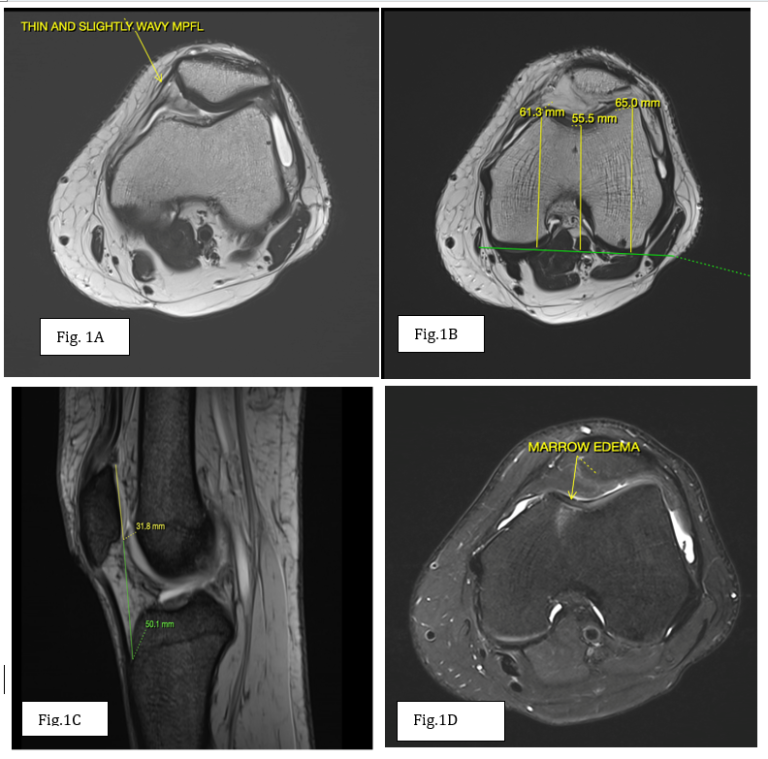

Comparison of the presented case with control. Knee MRI, axial plane ...

Lax Medial Patellofemoral Ligament Syndrome as a Cause of Recurrent ...

Clinics in diagnostic imaging (163) | SMJ

:: KJR :: Korean Journal of Radiology

Experimental and Therapeutic Medicine